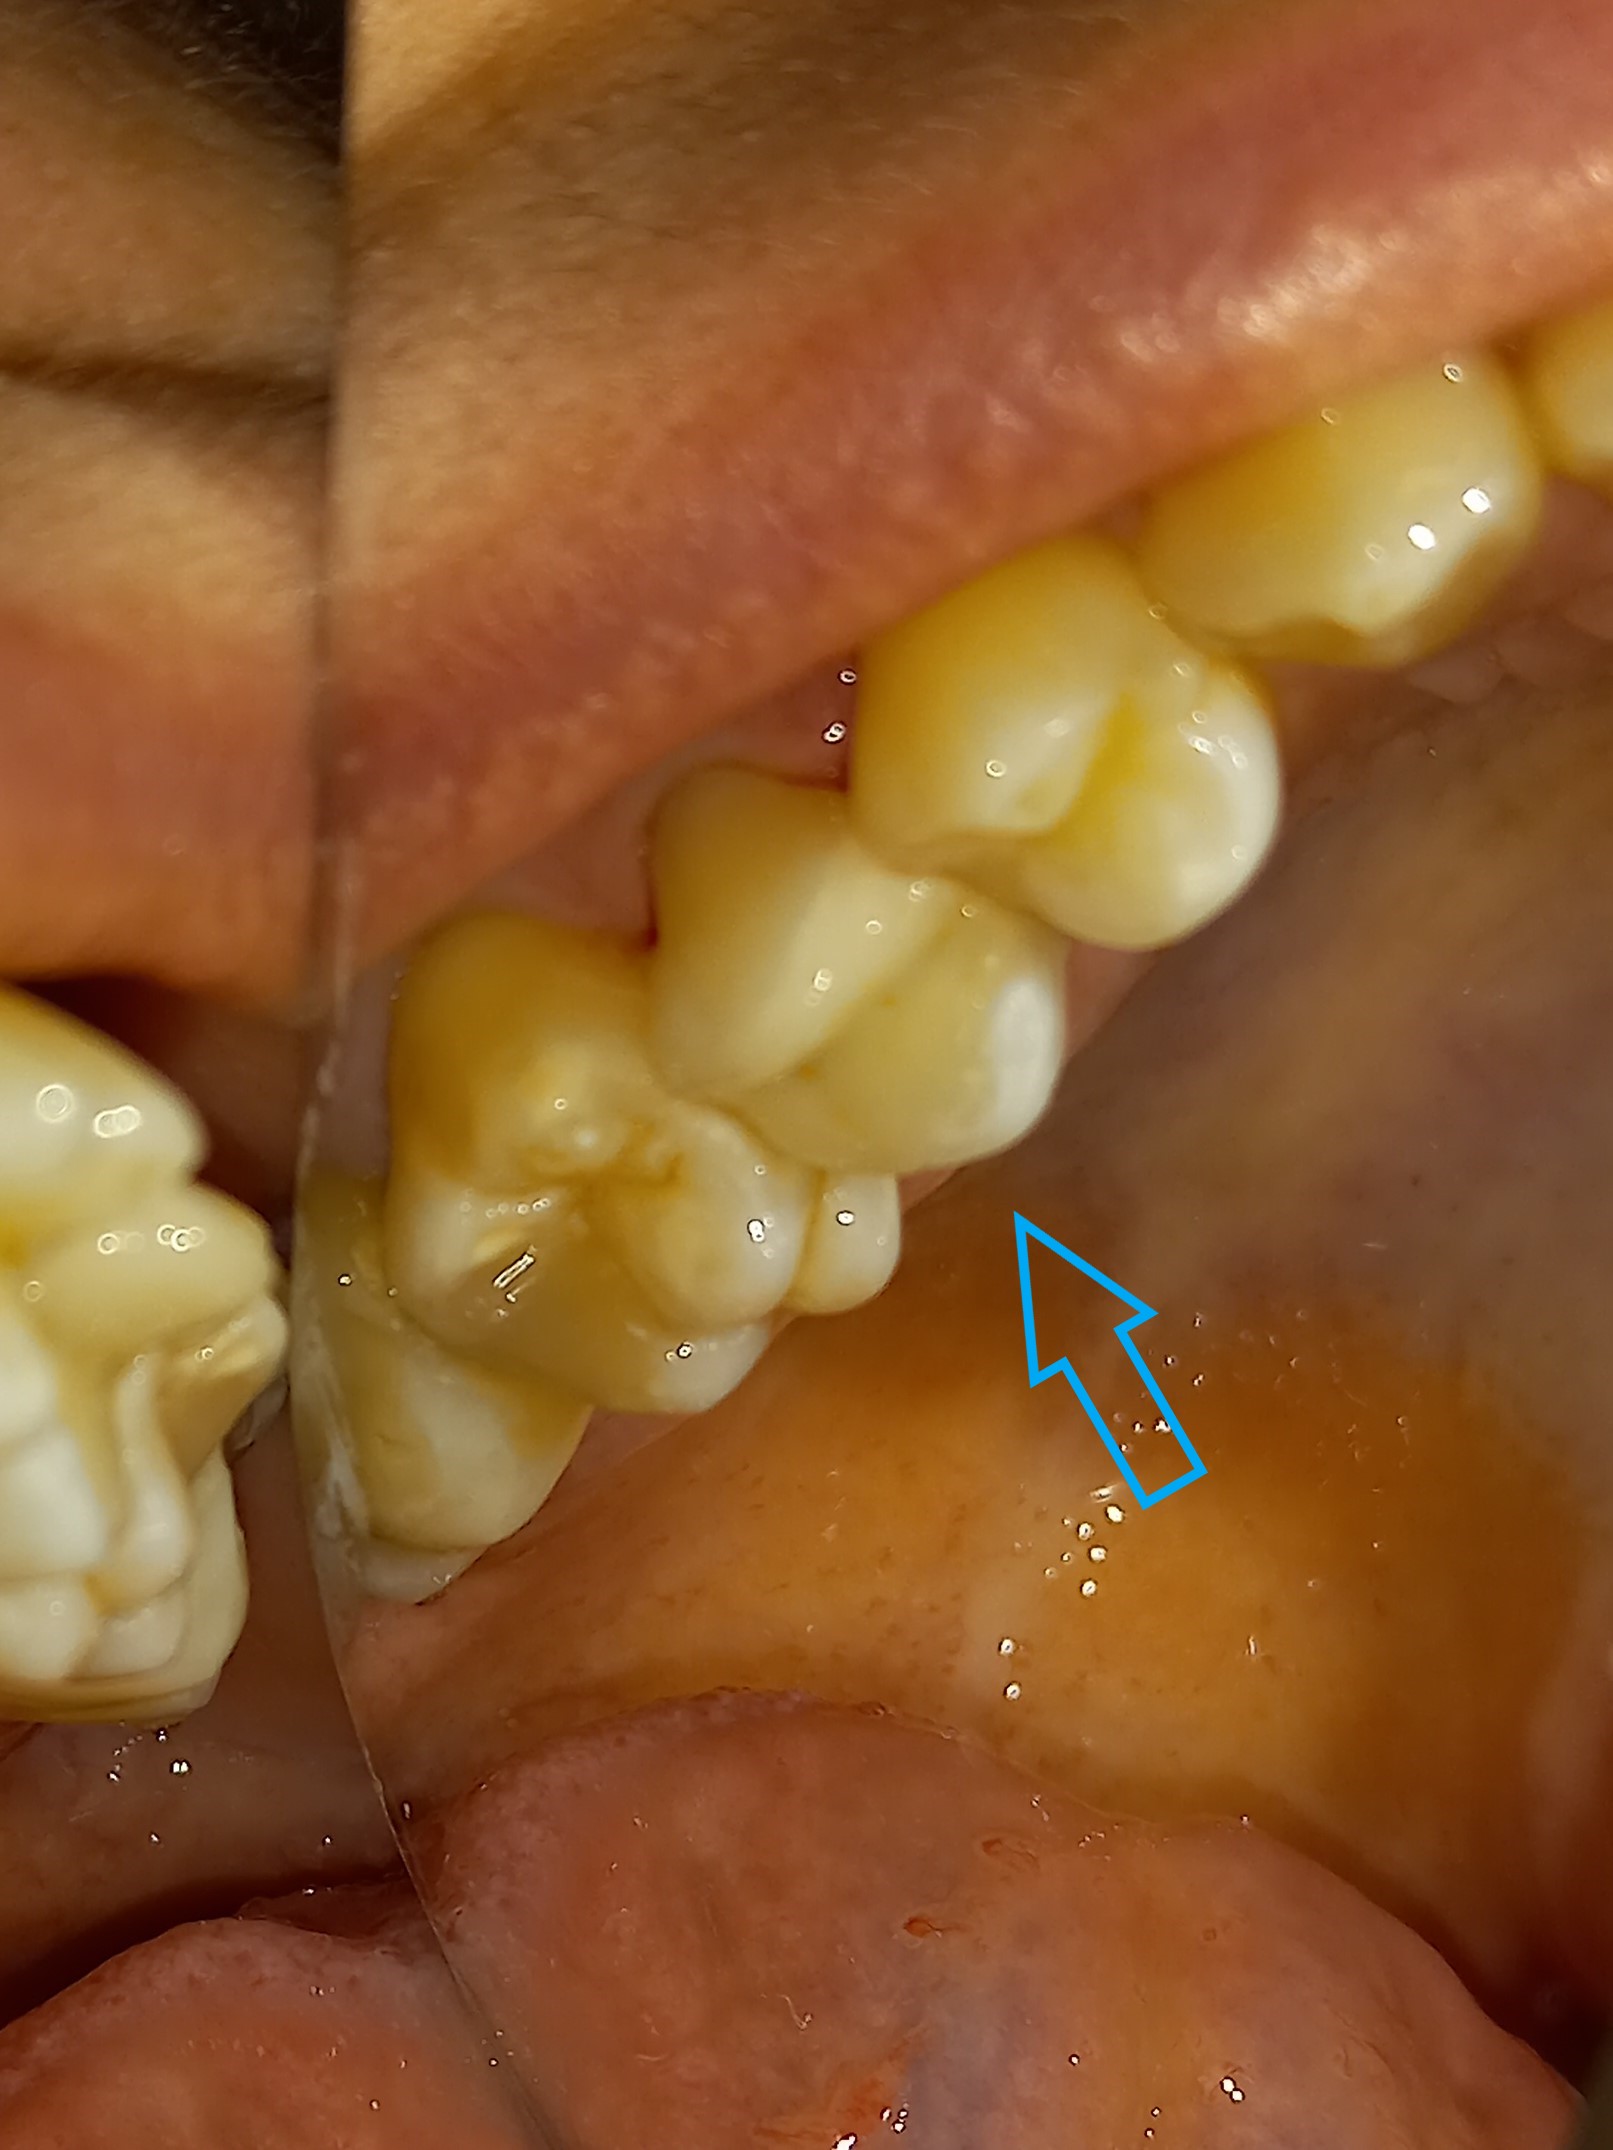

Ο ασθενής προσήλθε πρησμένος στην αριστερή πλευρά της κάτω γνάθου. Το πρόβλημα αφορούσε δύο γομφίους, από τους οποίους ο ένας ήταν ήδη απονευρωμένος και ο άλλος είχε βαθύ σφράγισμα, το οποίο έφτανε στο ύψος του νεύρου του δοντιού. Μετά την κλινική και ακτινογραφική εξέταση του δοντιού αποφασίστηκε η απονεύρωση του ενός γομφίου και η επανάληψη απονεύρωσης του άλλου γομφίου. Στο τέλος τα δύο δόντια θα προστατευτούν με θήκες δοντιών, εφόσον τα οδοντικά ελλείμματα ήταν μεγάλα.

Αρχική κλινική εικόνα του ήδη απονευρωμένου πρώτου γομφίου

Οι δύο γομφίοι μετά την ανασύστασή τους

Τελική εικόνα των δύο θηκών στους γομφίους